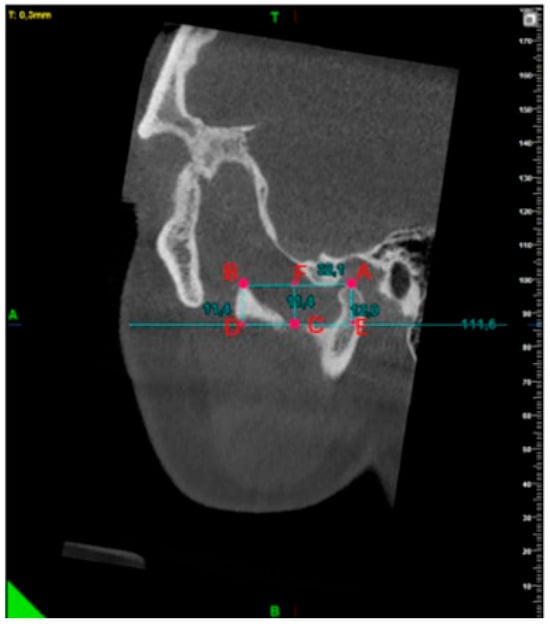

A Morphometric Evaluation of the Mandibular Condyle, Coronoid Process, and Gonial Angle: Age and Gender Differences in CBCT Imaging

2. Materials and Methods